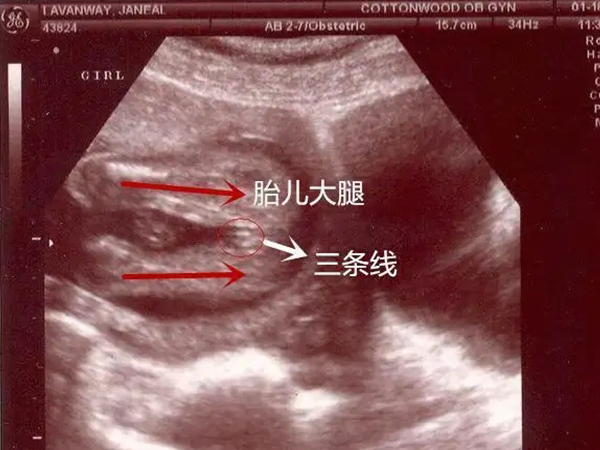

B超中有比较长的三条线是女儿的预兆

孕妇都会在产检的时候做B超检查,这是确保胎儿正常发育的一种手段,但是很多人不知道B超单中有四处细节已经暗示了胎儿性别,下面就给大家详细解释女孩B超单上会出现的细节暗示。

4、此外B超单上还会有三条线的显示,一般情况下三条线的长度比较长且比较亮,说明怀的是女孩,而三条线的长度很短,类似三个亮点说明怀的是男孩。